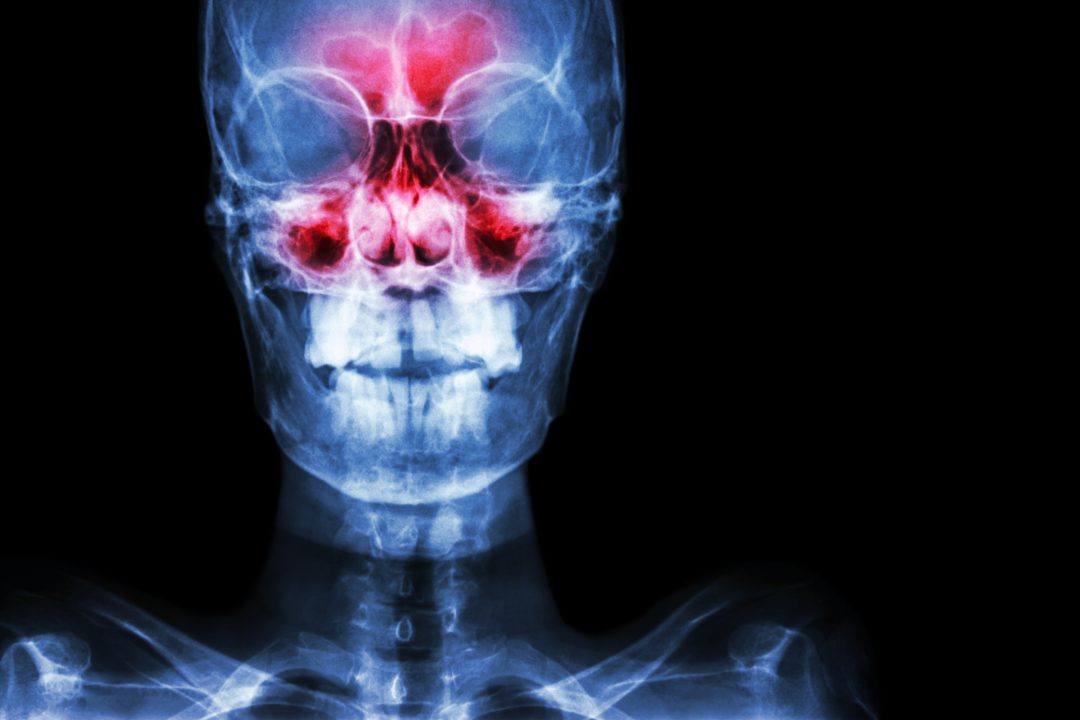

Chronic sinus inflammation alters brain activity

New research links sinus inflammation with alterations in brain activity, specifically with the neural networks that modulate cognition, introspection and response to external stimuli.

The scans enabled them to identify 22 people with moderate or severe sinus inflammation as well as an age- and gender-matched control group of 22 with no sinus inflammation. Functional MRI (fMRI) scans, which detect cerebral blood flow and neuronal activity, showed these distinguishing features in the study subjects:

- decreased functional connectivity in the frontoparietal network, a regional hub for executive function, maintaining attention and problem-solving;

- increased functional connectivity to two nodes in the default-mode network, which influences self-reference and is active during wakeful rest and mind-wandering;

- decreased functional connectivity in the salience network, which is involved in detecting and integrating external stimuli, communication and social behavior.